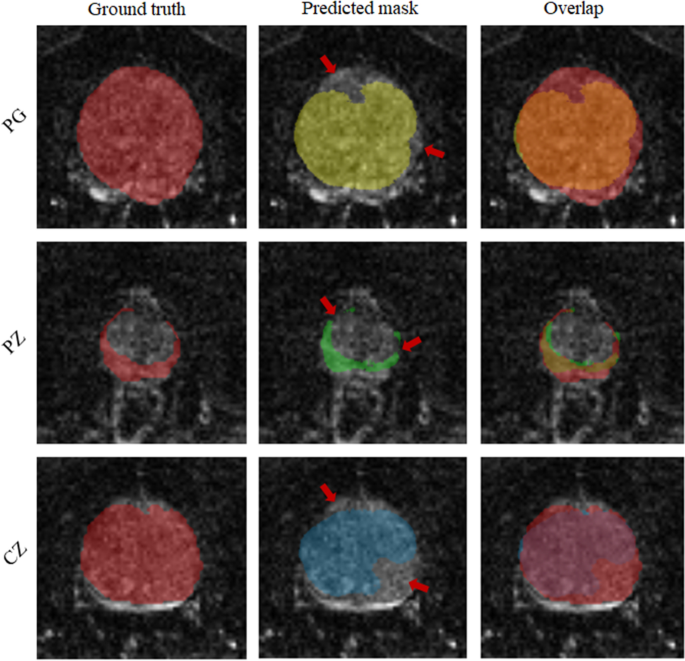

Unlike IMs, the UM showed a significantly higher DS when using MRE data in comparison with MRI data (p < 0.001, 0.05, and 0.05 for PG, CZ, and PZ, respectively). Overall, IMs had significantly more accurate results compared with the UM in terms of both DS and HD with p-values < 0.01 for PG, CZ, and PZ. This is shown in Fig. 7, illustrating that DS was higher and HD lower for IMs than for the UM. Figure 8 shows a case where model segmentations were inaccurate compared with the ground-truth masks. Quantitative analysis, for both IMs and the UM, of pixel values in PG, CZ, and PZ showed no significant difference (p>0.05) between ground-truth and automated prostate segmentation. Group mean values are presented in Tables 4 and 5.

Illustration of inaccurate segmentations: left column is the ground truth; middle is predicted masks and right is the overlap between ground truth and predicted masks. Rows from top to bottom, images of PG, PZ and CZ respectively.

Figure 8 shows a case where the model failed to achieve accurate segmentation. Inaccuracies appear to be attributable to under-segmentation and discontinuity. Under-segmentation is visible in both the entire prostate gland (first row) and the CZ (last row), where the model did not properly locate and delineate boundaries. Discontinuity can be seen in the PZ (middle row), where the model resulted in a mask with several unconnected neighboring areas. Many factors can contribute to inaccurate segmentation, including boundary ambiguity, partial volume effects, and tissue heterogeneity. Therefore, radiologists typically use 3D information, which is subjectively interpolated by eye to the ambiguous image slice. However, even including adjacent slices for training in a 2.5-D approach51 or use of full 3D models does not necessarily lead to better segmentation performance due to partial volume effects52 .